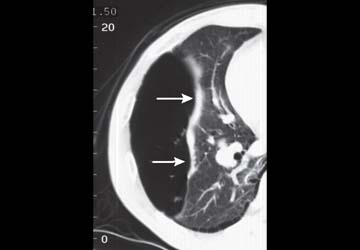

Chest CT: Extensive postoperative subcutaneous emphysema and pneumomediastinum. There is a moderate left-sided pneumothorax after left upper partial lobectomy, despite the presence o left chest tube with its lip at the left ape

Progression of subcutaneous emphysema following thoracic surgery should raise the suspicion for a posible bronchial leak